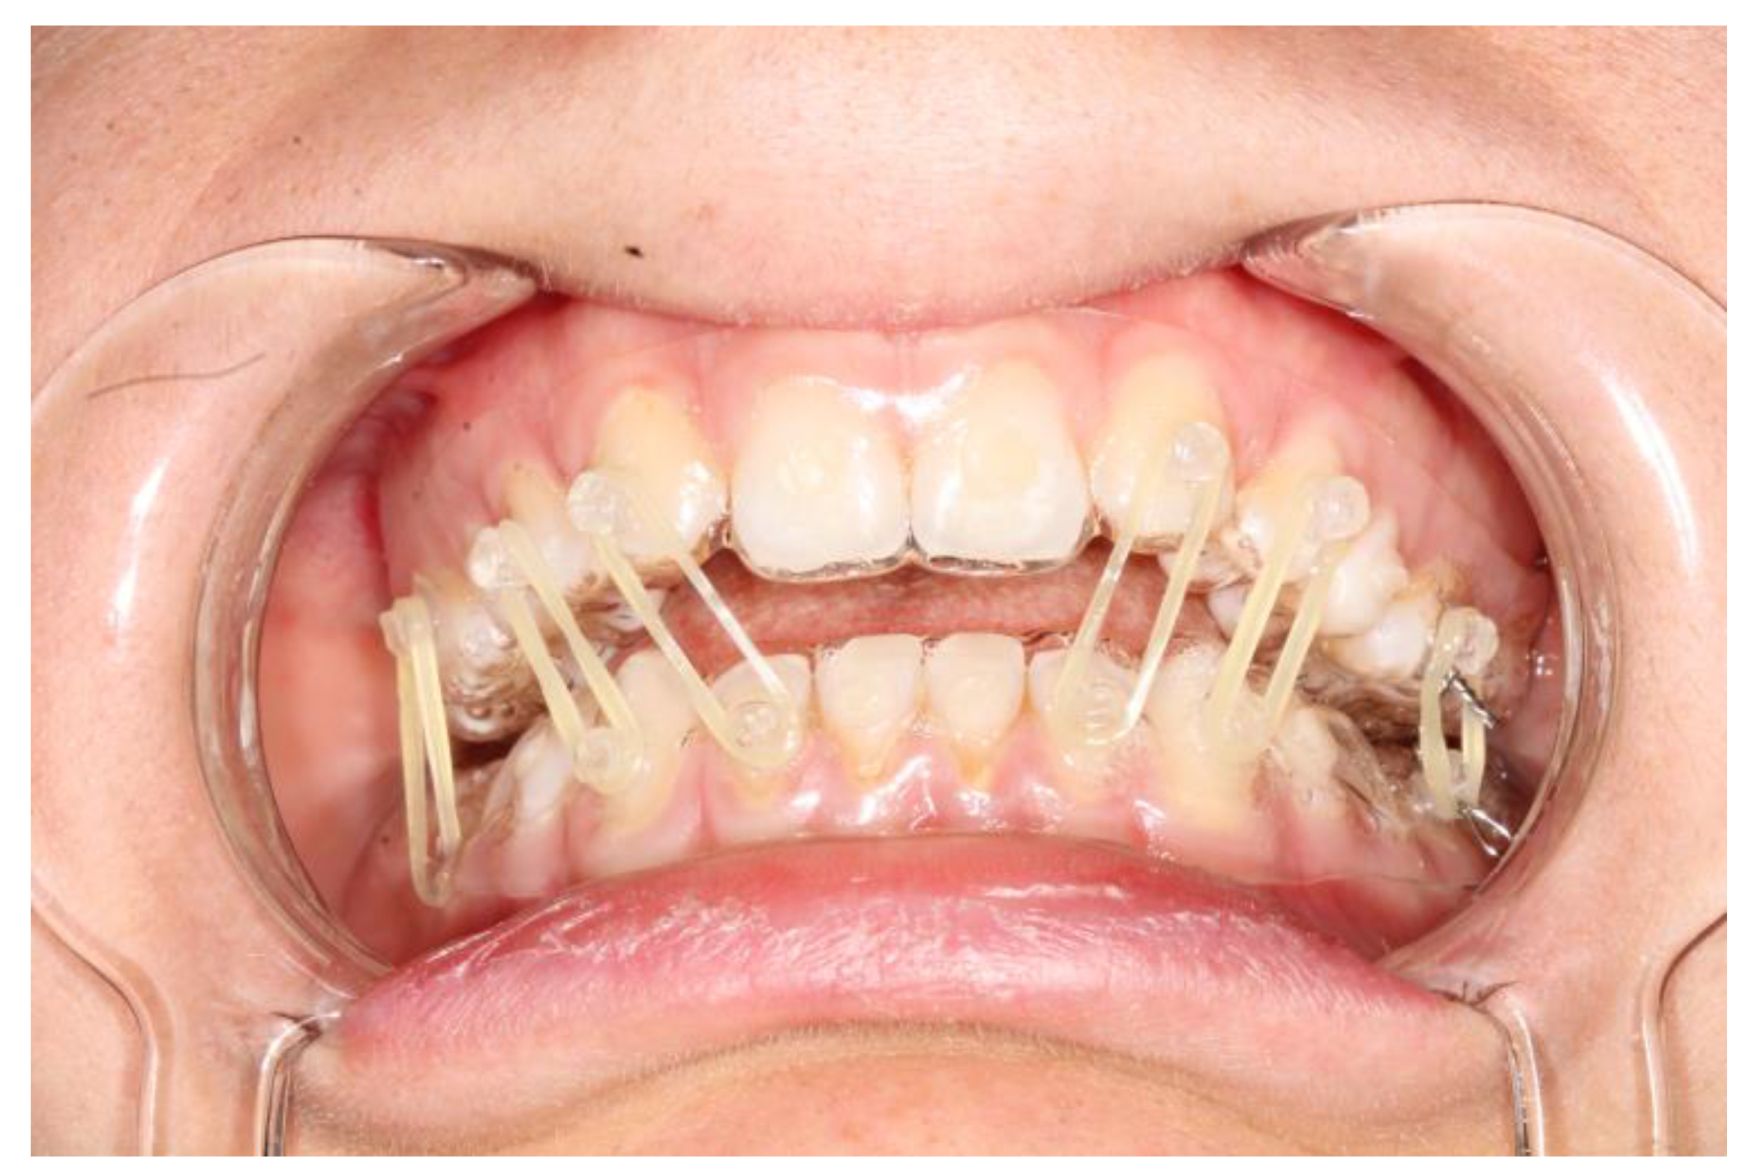

The fixation strength of the intermaxillary fixation was considered adequate in both cases (Figure 5 and Figure 6).

Occlusion and periodontal tissue were within normal clinical ranges after the treatment (Figure 6).

Figure 5. Intraoral view of patient 2 during the treatment; is it possible to note the slight problem with oral hygiene, which is nonetheless completely acceptable.